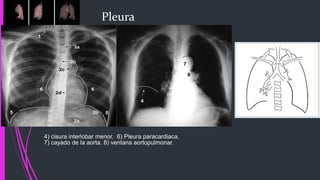

Pleura

4) cisura interlobar menor. 6) Pleura paracardiaca.

7) cayado de la aorta. 8) ventana aortopulmonar.